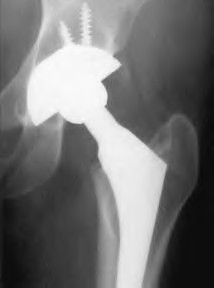

A 45-year-old female with developmental dysplasia of the hip (DDH) presents for THA. Preoperative radiographs show the femoral head is subluxated, with 80% proximal migration relative to the height of the normal true acetabulum. Based on the Crowe classification, what type of dysplasia does she have?

Explanation